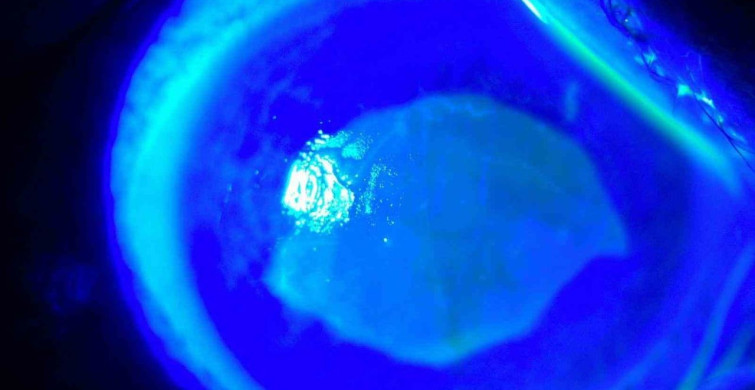

Göz Hastalıkları Uzmanı Doç. Dr. Ömer Faruk Yılmaz, "Hastamız, kırlangıç otu suyunu damlattıktan sonra gözlerini açamaz hale geldi. Görüş alanı tamamen kayboldu ve kornealarında ciddi tahribat meydana geldi" dedi. Hastanın tedavi sürecine dair bilgi veren Yılmaz, doğru tedavi ile hastanın sağlığına kavuştuğunu belirtti.

Hastanın göz muayenesinde kornea epitelinin tahrip olduğu belirlendi ve hızlı bir tedavi süreci başlatıldı. Yılmaz, "Tedavi sürecimiz yaklaşık 2 hafta sürdü ve sonunda hastamız tamamen iyileşti" diye ekledi.